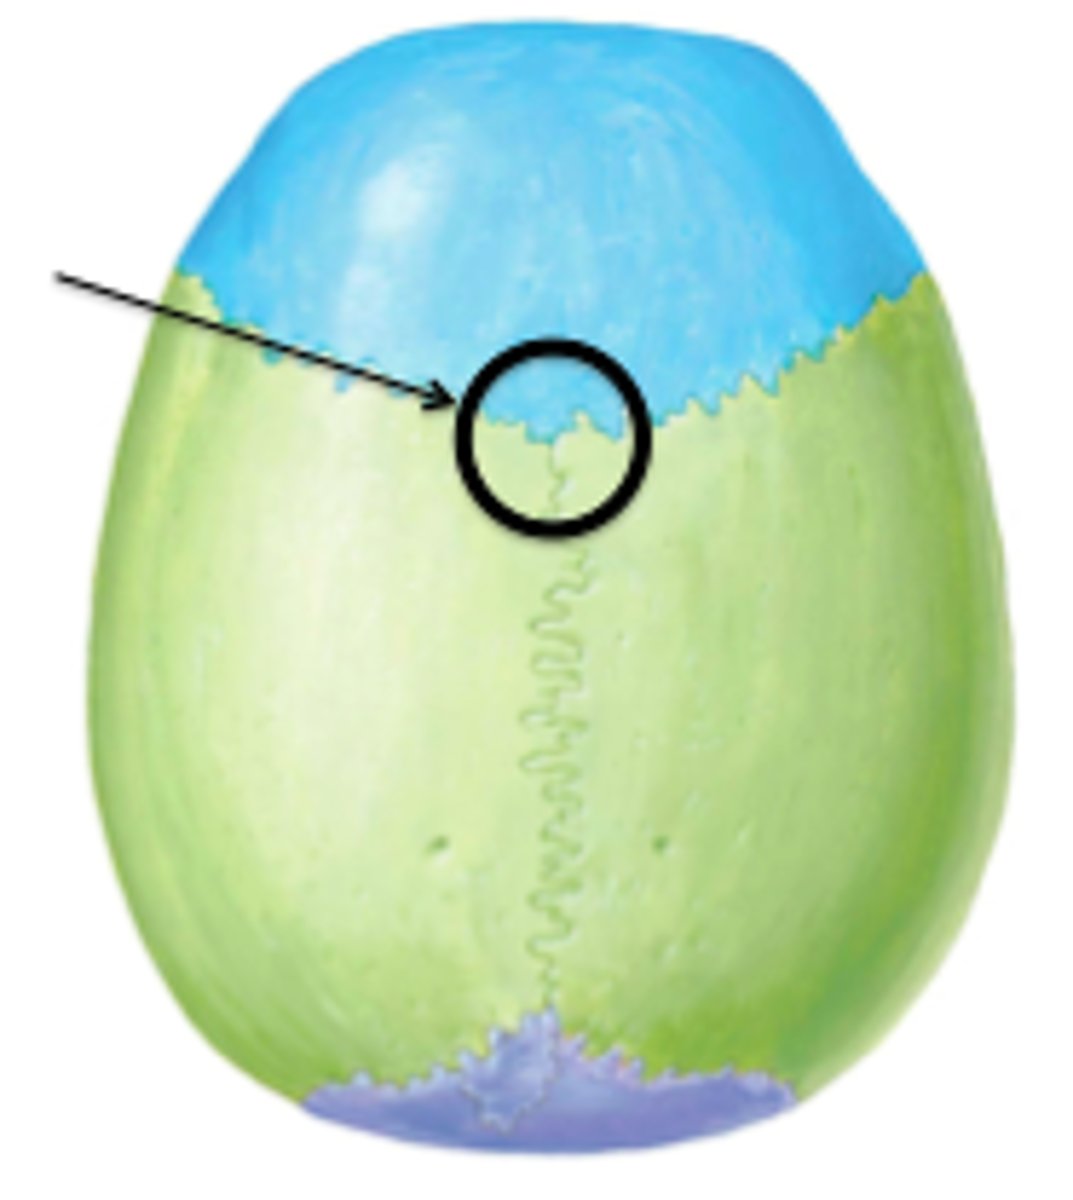

bregma

lambda